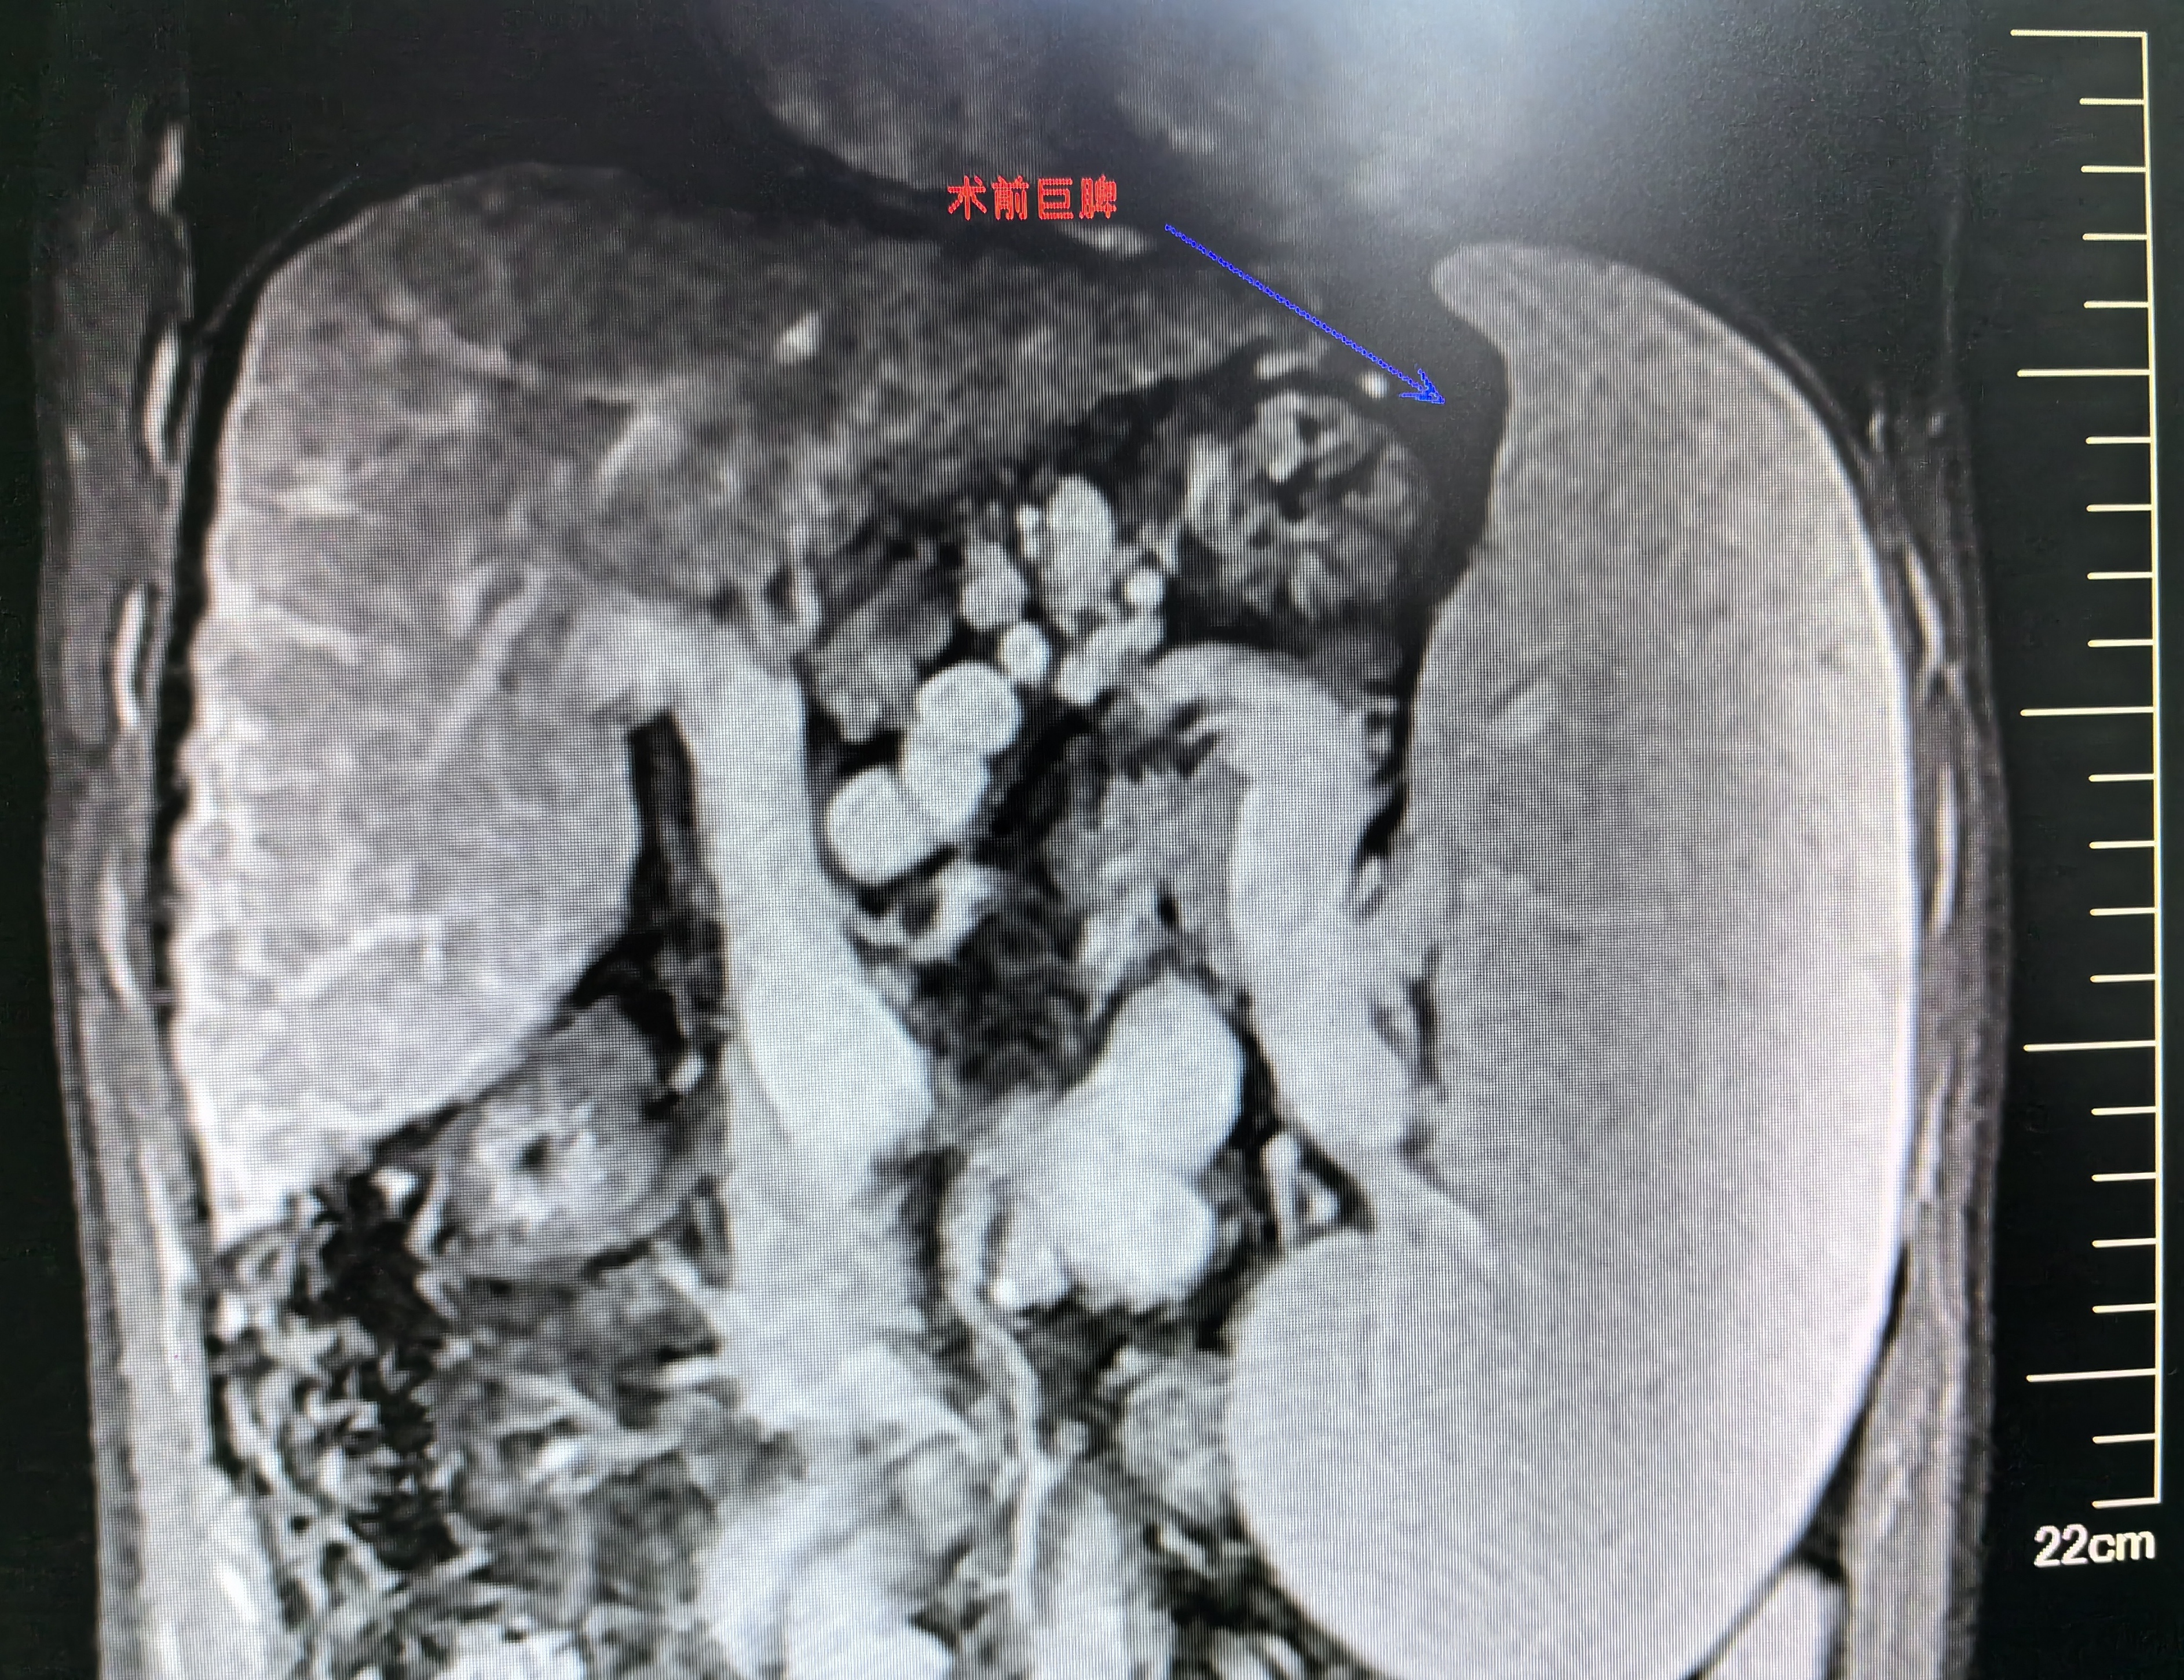

肝豆?fàn)詈俗冃詫?dǎo)致的門脈高壓癥行脾部分切除斷流術(shù)治療

患者中年男性,肝豆?fàn)詈俗冃圆∈范嗄?,口服硫酸鋅片、二巰丁二酸膠囊治療?;颊唛g斷黑便,長(zhǎng)年貧血,化驗(yàn)顯示血色素顯著降低,白細(xì)胞、血小板顯著降低。凝血酶原時(shí)間延長(zhǎng)、凝血酶原活動(dòng)度下降。胃鏡檢查是食管胃底靜脈重度曲張,紅色征陽(yáng)性。腹部影像學(xué)檢查示肝硬化明顯,巨脾。因食道胃底靜脈重度曲張導(dǎo)致反復(fù)黑便及巨脾導(dǎo)致腹脹、白細(xì)胞血小板顯著降低,給予行脾部分切除斷流術(shù),解除脾大脾功能亢進(jìn),保留部分脾臟功能,降低食道胃底曲張靜脈破裂出血風(fēng)險(xiǎn)。手術(shù)順利,術(shù)后恢復(fù)順利出院。術(shù)后4月再次入院復(fù)查?;颊呔駹顟B(tài)好,進(jìn)食增加,體力明顯增加,腹脹消失,未再黑便,白細(xì)胞、血小板恢復(fù)正常,血色素恢復(fù)正常,凝血功能恢復(fù)正常。肝功能可。食道內(nèi)外靜脈曲張較前緩解,剩余脾臟維持在正常大小范圍,存活良好。治療效果不錯(cuò)。